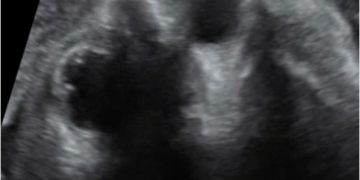

How To Do Giugno 2024: diagnosi e gestione delle anemie fetali

Cari soci, questo mese un nuovo video "How to do", dedicato alla diagnosi e alla gestione delle anemie fetali. Grazie a Tiziana Fanelli! Il video è accessibile ai soli soci...